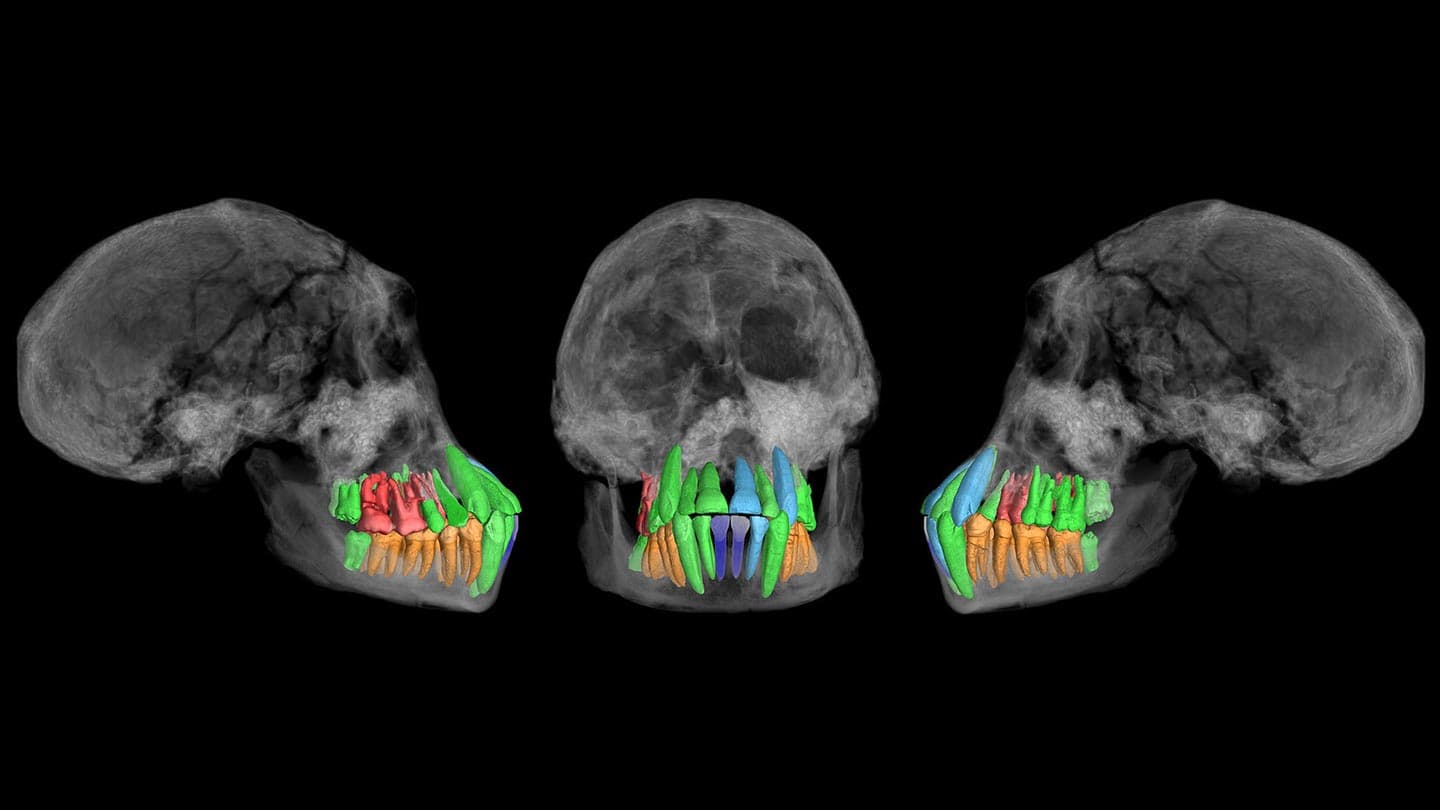

X-ray imaging views of an susceptible Homo cranium from Dmanisi, Georgia, expose enamel veteran in a fresh analysis of dental trend in green. Enamel shown in orange and crimson weren’t incorporated in the look. Re-creations of enamel missing from the cranium seem in gentle blue and darkish blue.

Vincent Beyrand and Paul Tafforeau/European Synchrotron Radiation Facility, Grenoble, France

Their outcomes, based entirely totally on X-ray imaging abilities that examined microscopic development traces for the length of the fossil enamel, seem November 13 in Nature.

X-ray imaging allowed the researchers to estimate the extent of enamel development at diverse ages for the length of the existence of the Homo childhood, who died appropriate ahead of reaching dental maturity between 12 and 13.5 years of age.